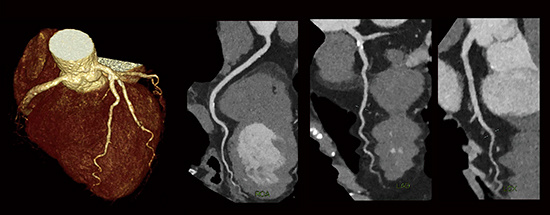

IQonにおける仮想単色X線(以下,MonoE)を用いた画像は,エネルギーを40keVから200keVまで連続的に可変して表示することができる。また,上記のanti-correlated noiseを除去することで,低いエネルギーのMonoE画像(以下,MonoE低keV画像)において,造影剤投与量を低減しても高画質で観察が可能となる。図3の腎機能低下症例では,造影剤を大幅に低減し,MonoE低keV画像を使用することで,低侵襲で診断能の高い検査が可能となっている。また,物質弁別を用いたヨード密度強調画像(以下,Iodine no water)では,ヨード造影剤のコントラストを強調することにより造影効果を有する箇所はさらに視認性が増し,従来のSECTでは診断困難なステント内再狭窄症例における低吸収プラークの視認性向上が期待できる(図4)。

図4 ステント内再狭窄症例

→:低吸収プラーク

a:従来画像 120kVp b:Iodine no water c:angiography